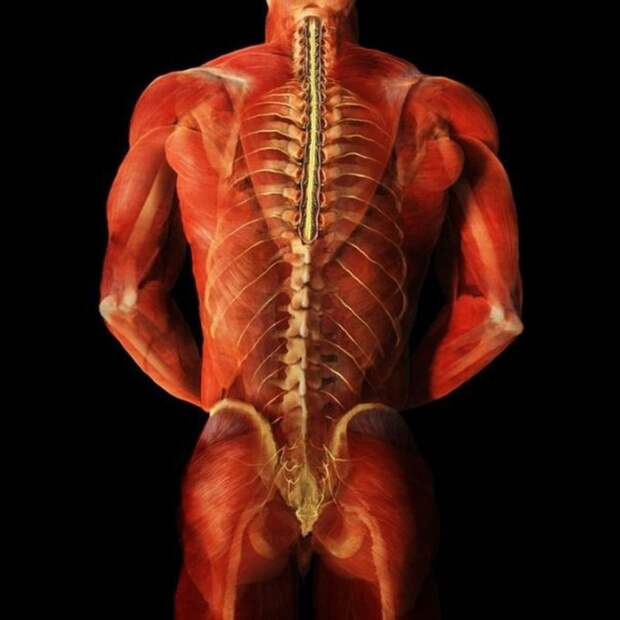

Позвоночный столб и мышцы